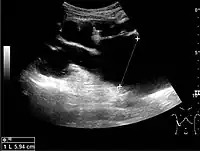

Cortical thickness should be estimated from the base of the pyramid and is generally 7–10 mm. If the pyramids are difficult to differentiate, the parenchymal thickness can be measured instead and should be 15–20 mm (Figure 3). The echogenicity of the cortex decreases with age and is less echogenic than or equal to the liver and spleen at the same depth in individuals older than six months. In neonates and children up to six months of age, the cortex is more echogenic than the liver and spleen when compared at the same depth.[1]

The hydronephrosis is typically graded visually and can be divided into five categories going from a slight expansion of the renal pelvis to end-stage hydronephrosis with cortical thinning (Figure 15). The evaluation of hydronephrosis can also include measures of calyces at the level of the neck in the longitudinal scan plane, of the dilated renal pelvis in the transverse scan plane and the cortical thickness, as explained previously (Figure 16 and Figure 17).[1]